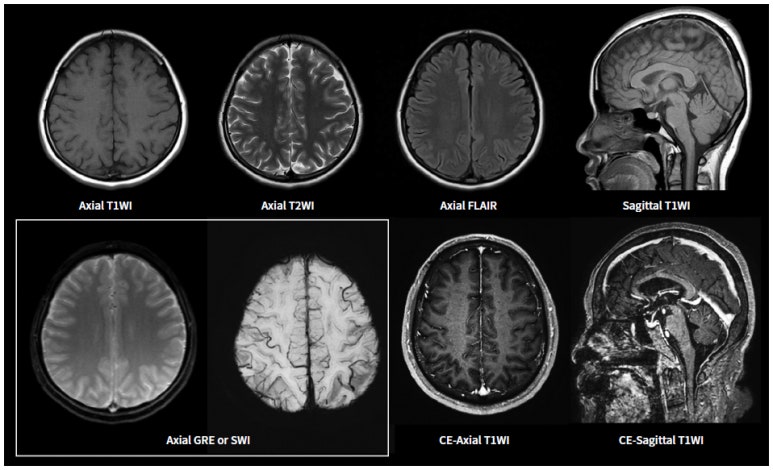

MRI 검사의 다양한 시퀀스

MRI는 뇌를 더 정밀하고 입체적으로 관찰할 수 있는 검사입니다.

단순히 영상을 한 장 찍는 것이 아니라, 여러 종류의 시퀀스(Sequence)를 통해 다양한 방식으로 뇌를 분석합니다.

MRI의 시퀀스는 같은 부위를 서로 다른 조건으로 여러 장 촬영하는 방식입니다.

쉽게 말하면, 같은 장면을 낮, 밤, 적외선 카메라로 각각 보는 것처럼 다양한 정보와 상태를 동시에 파악할 수 있습니다.